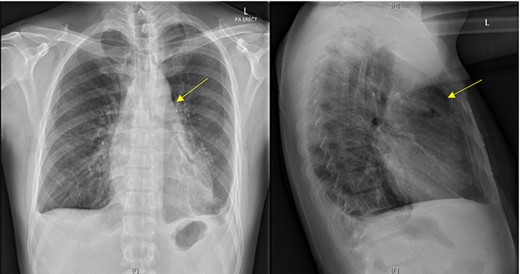

Initial chest X-ray demonstrated lucency over the left heart border and anterior mediastinum suggesting pneumopericardium (Fig. 1). A computed tomography (CT) scan of the chest demonstrated multiple pericardial collections containing loculated gas and fluid with calcification causing stenosis of the superior vena cava. An OPF was suspected (Fig. 2). Bilateral tree-in-bud nodularity reflecting active pulmonary infection with diffuse bronchitis and endobronchial plugging were also present.

Postero-anterior erect and lateral chest radiograph. Lucency over the left heart border and anterior middle mediastinum consistent with a pneumopericardium.